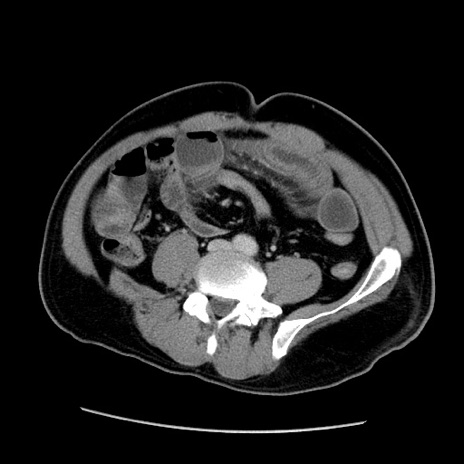

症例22(横断像)

【症例】50歳代男性

【主訴】腹痛

【現病歴】AVMからの被殻出血のため回復期リハ病棟入院中。 本日午後3時頃急に下腹部痛が出現した。

【既往歴】AVM、被殻出血、虫垂炎、高血圧

【身体所見】意識晴明、左半身不全麻痺、会話の理解は良好、36.5°C、腹部:膨隆、全体に板状硬、下腹部正中に圧痛点あり、反跳痛-、筋性防御不明、右下腹部にope scar

【データ】WBC 9400、CRP 0.06